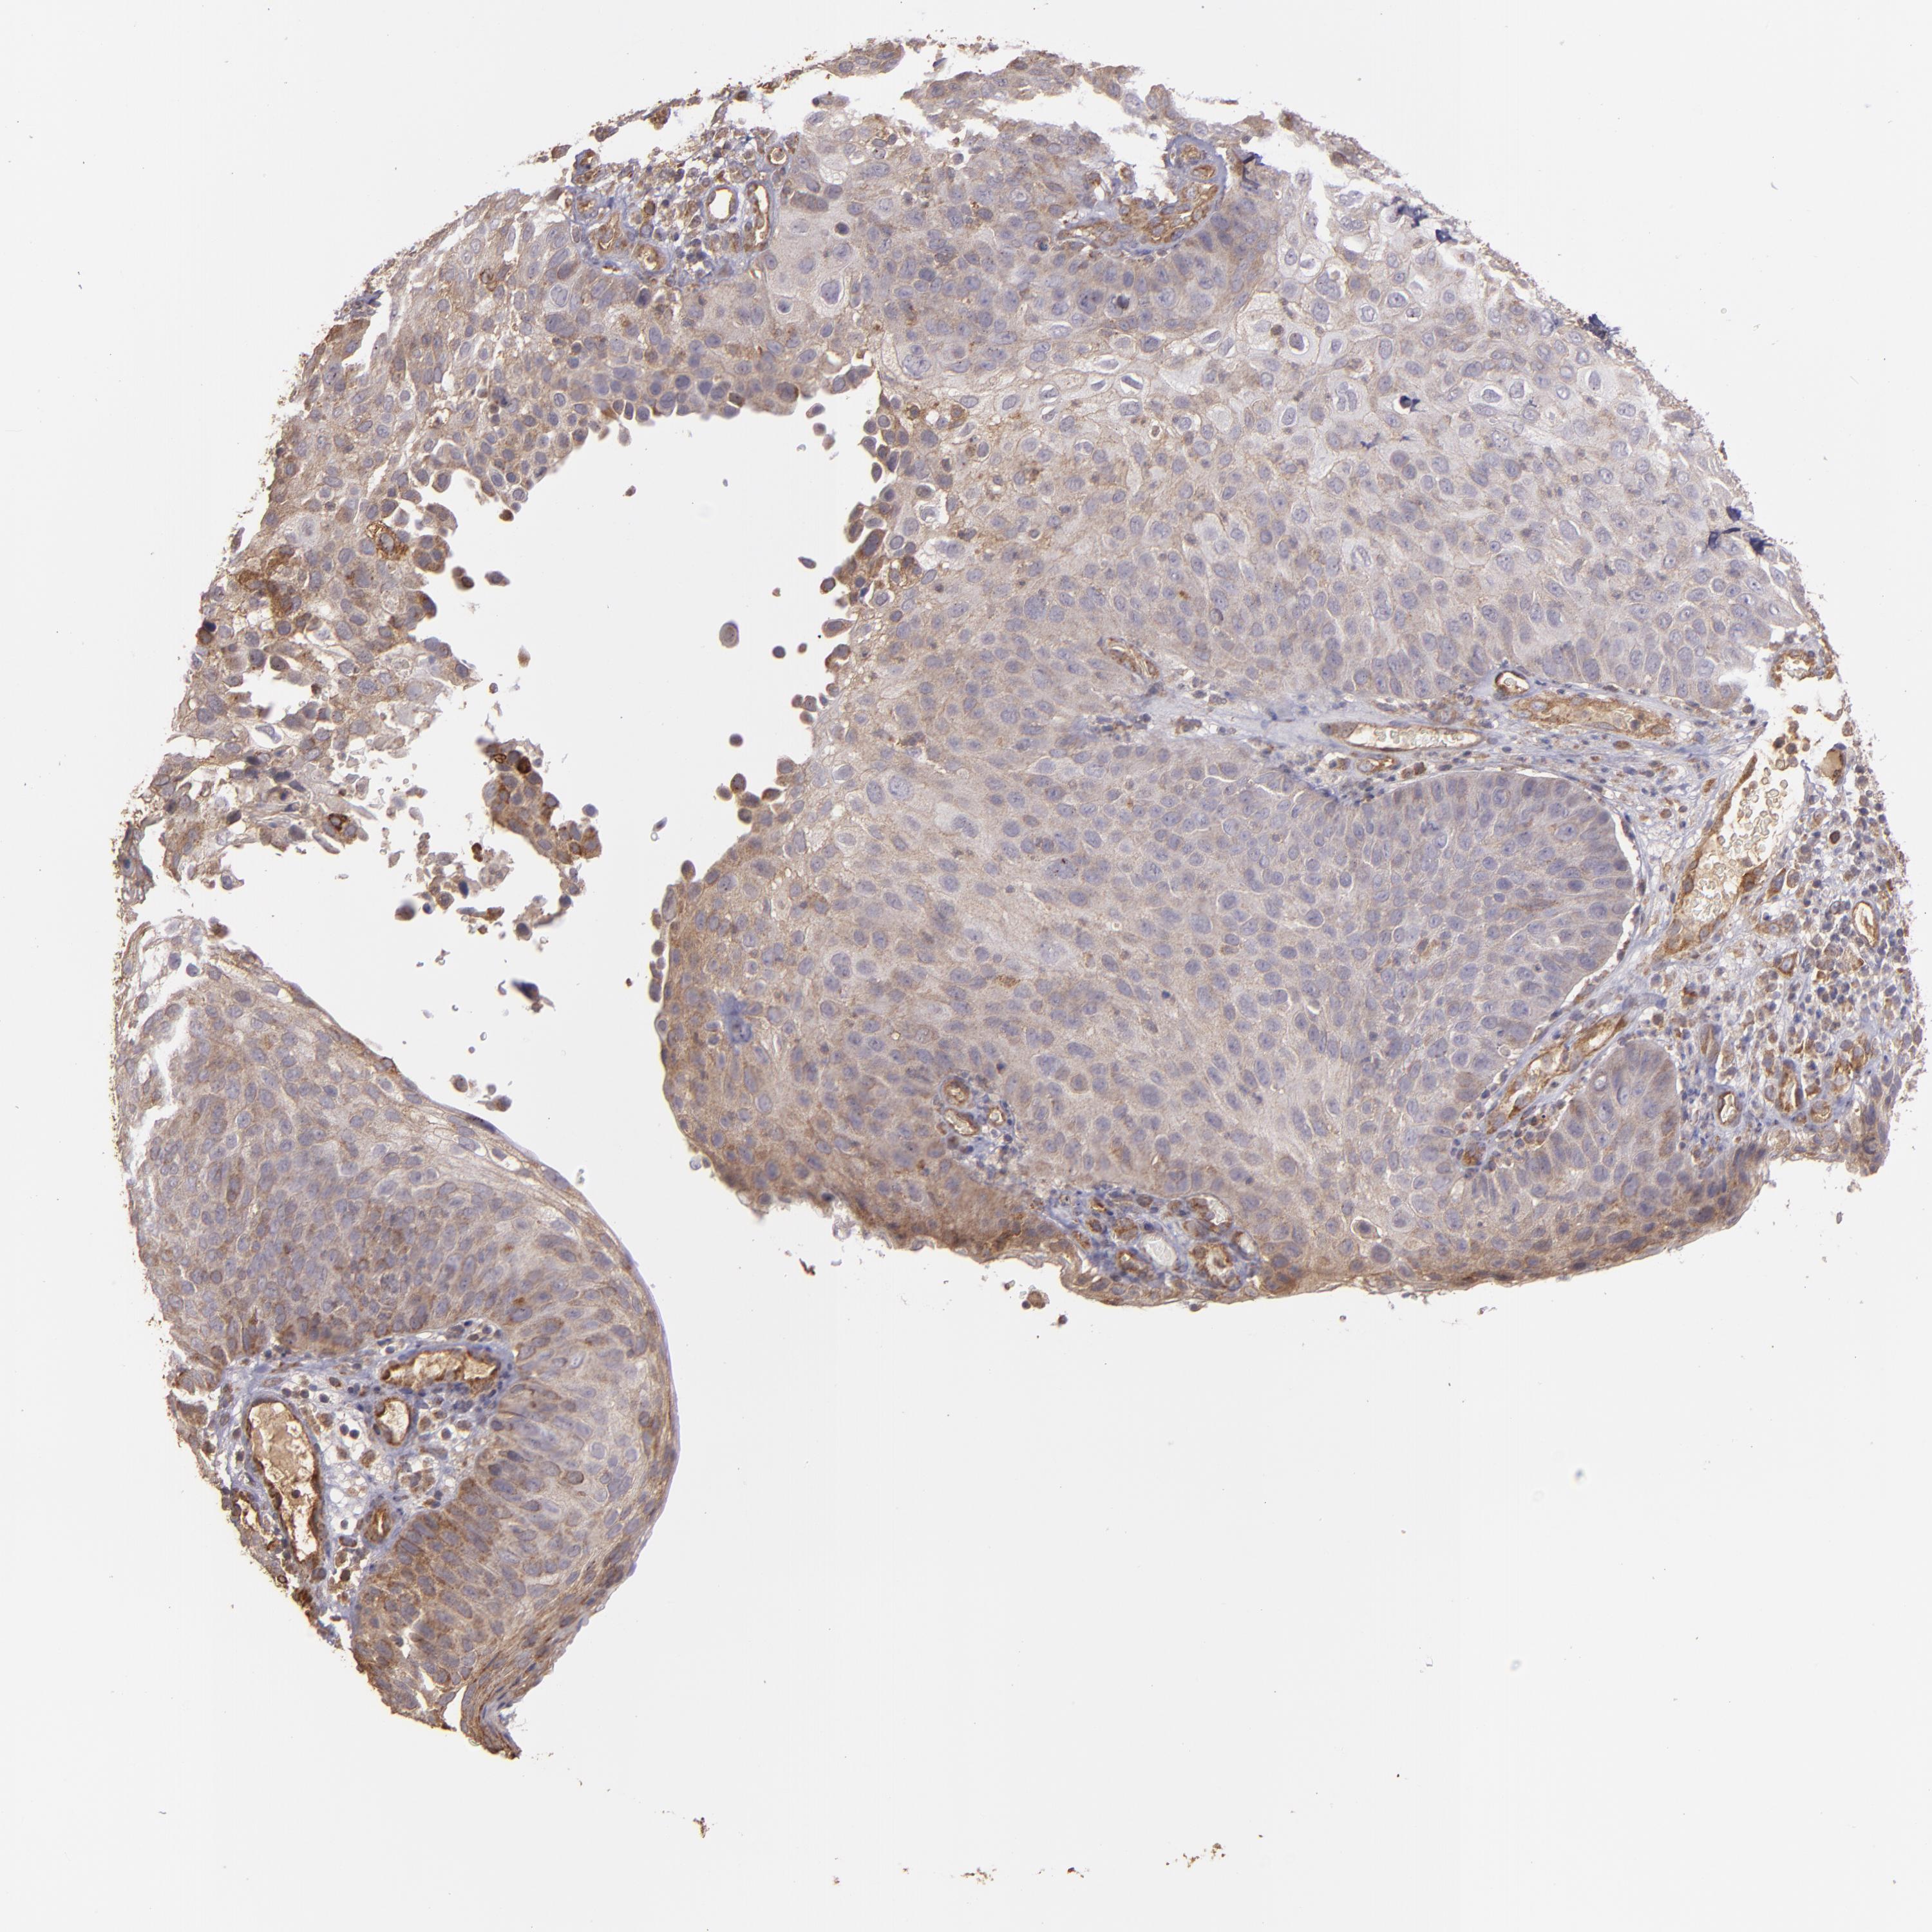

Basal cell and squamous cell cancer

SKIN CANCER - Protein expressioni

A mouse-over function shows sample information and annotation data. Click on an image to view it in a full screen mode. Samples can be filtered based on level of antibody staining by selecting one or several of the following categories: high, medium, low and not detected. The assay and annotation is described here.

Antibody stainingi

Antibody staining in the annotated cell types in the current human tissue is reported as not detected, low, medium, or high, based on conventional immunohistochemistry profiling in selected tissues. This score is based on the combination of the staining intensity and fraction of stained cells.

Each image is clickable and will lead to virtual microscopy that enables deeper exploration of all samples and also displays staining intensity scores, fraction scores and subcellular localization as well as patient and tissue information for each sample.

Antibody HPA001490

Antibody HPA013616

Staining

High

Medium

Low

Not detected

Intensity

Strong

Moderate

Weak

Negative

Quantity

>75%

75%-25%

<25%

None

Location

Nuclear

Cytoplasmic/membranous

Cytoplasmic/membranous,nuclear

Squamous cell carcinoma, NOS

Basal cell carcinoma